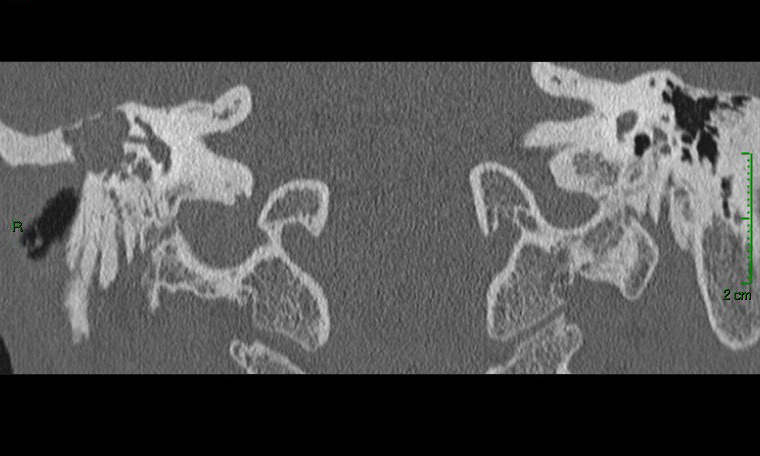

Devant ces atteintes multiples, vous demandez un scanner et une imagerie par résonance magnétique (IRM) en urgence qui sont représentés ci-dessous.

Question 11 : Qu’en pensez-vous ?

Question difficile, à laquelle on peut (et doit) répondre avec la clinique. En effet, le canal est ouvert sur le scanner (en coupe coronale sur la figure 4), mais surtout on peut le déduire devant le fait que le patient a un nystagmus avec un cholestéatome

La cavité de l’oreille est noire : donc il y a de l’air. Elle n’est pas comblée par du tissu

Faux, le scanner montre un comblement aspécifique, sans différencier tissu, liquide ou fibrose

Avec la séquence de diffusion à droite, qui est pathognomonique du cholestéatome

C’est une séquence de diffusion

L’IRM est le seul examen pathognomonique du cholestéatome. Le scanner montre la lyse osseuse mais n’est pas du tout spécifique de l’atteinte. Il n’est pas nécessaire de connaître les structures de l’oreille interne sur le scanner (qui sont très compliquées), mais il faut au moins reconnaître une oreille moyenne pleine (contenu gris) d’une oreille saine aérée (contenu en noir). On peut ensuite déduire de l’énoncé les destructions correspondantes. On aurait pu aussi dire dans cette question que le canal du nerf facial était détruit : c’est forcément le cas puisqu’il y a une atteinte du facial.